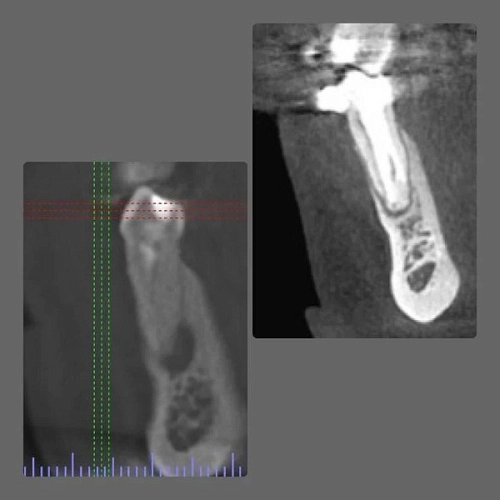

Для того, чтобы достоверно оценить анатомию зуба необходимо изучить компьютерную томографию, а иногда сделать дополнительно прицельный снимок.

Компьютерная томография показала воспаление у корня зуба на верхней челюсти слева. Причиной воспаления стал пропущенный канал в зубе.